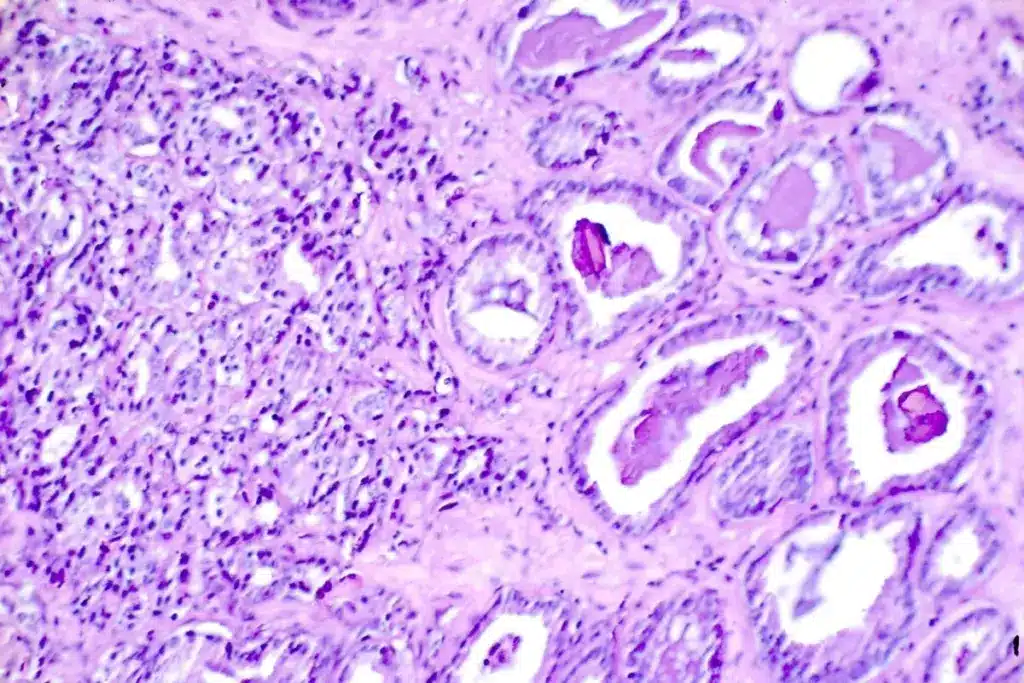

Biopsy and Other Procedures

Even with imaging tests, a biopsy might be needed to confirm bone metastasis. A biopsy takes tissue from the suspected area for a microscope check. It helps find out if the bone lesion is cancer and where it came from.

Other tests, like bone marrow aspiration, might also be done. These tests, along with imaging, help doctors make a precise diagnosis. This leads to a good treatment plan.